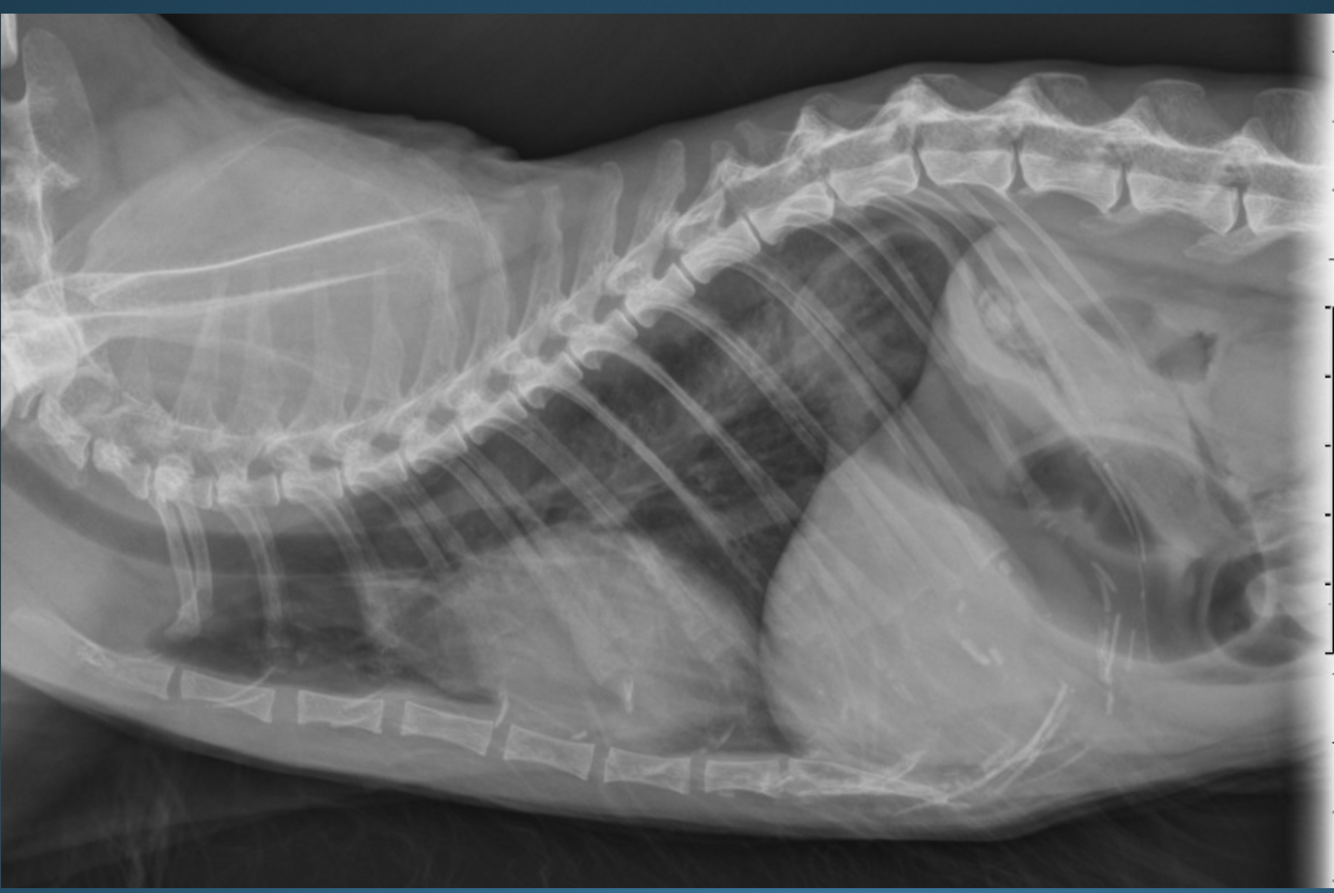

What is shown in these images?

gastric dilatation and volvulus

-“popeye arm” or “smurf hat”

-pylorus has moved dorsally and cranially; not seen well on VD view

-compartmentalization band seen

-pylorus is gas-filled on right lateral view